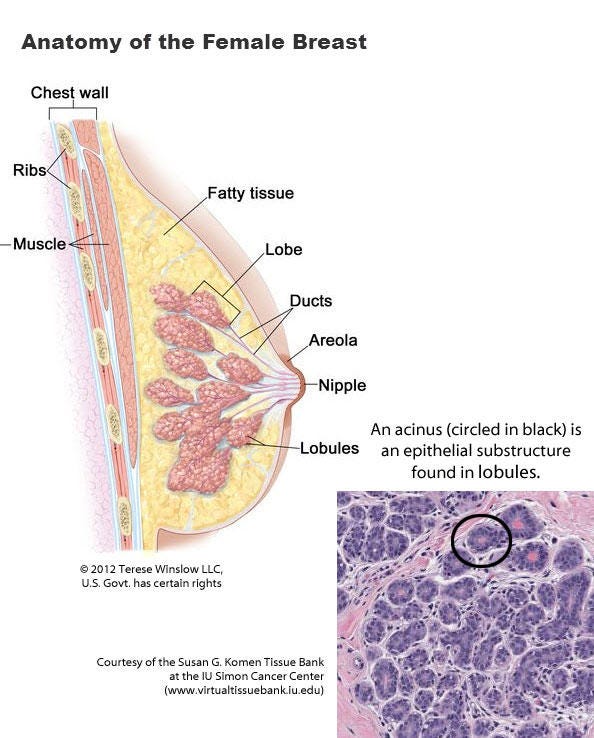

Breast anatomy and histology

Most cases of breast cancer arise from the progenitor or stem cells of the terminal duct lobular unit, part of the normal anatomy of the female breast:

Common breast cancer types are called ductal or lobular for historical reasons - they no longer accurately reflect our understanding of their origin.

Invasive duct carcinoma (IDC) of no special type arises from breast epithelial progenitor or stem cells in the terminal duct lobular unit, as do other types of breast carcinoma. Important prognostic factors are patient age, tumor stage, lymph node status, histologic grade, clinical biomarker profile and tumor gene expression signature. Patients are treated with surgical excision and possibly with radiotherapy, systemic chemotherapy or targeted therapies.